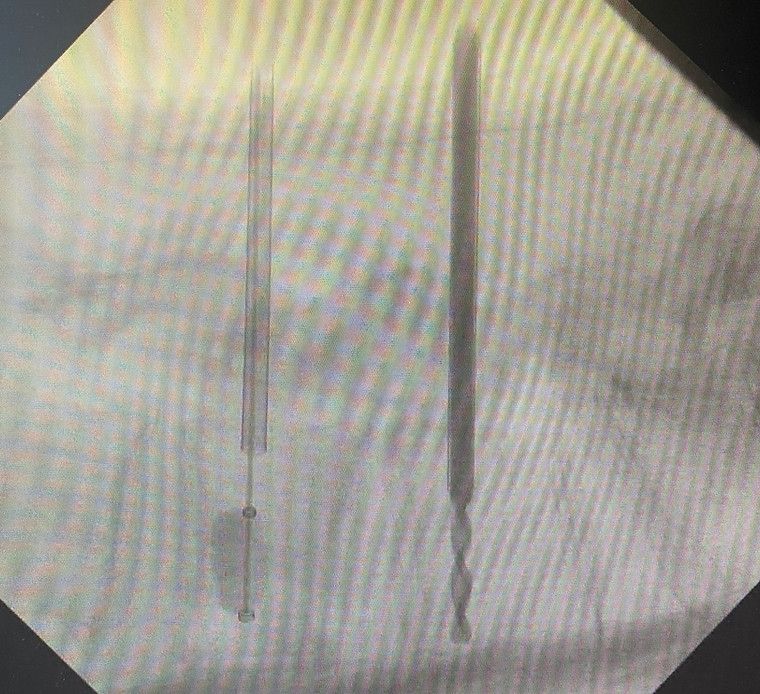

Mikrochirurgische Eingriffe

Es werden mikrochirurgische Bandscheibenoperationen und Dekompressionen durchgeführt.